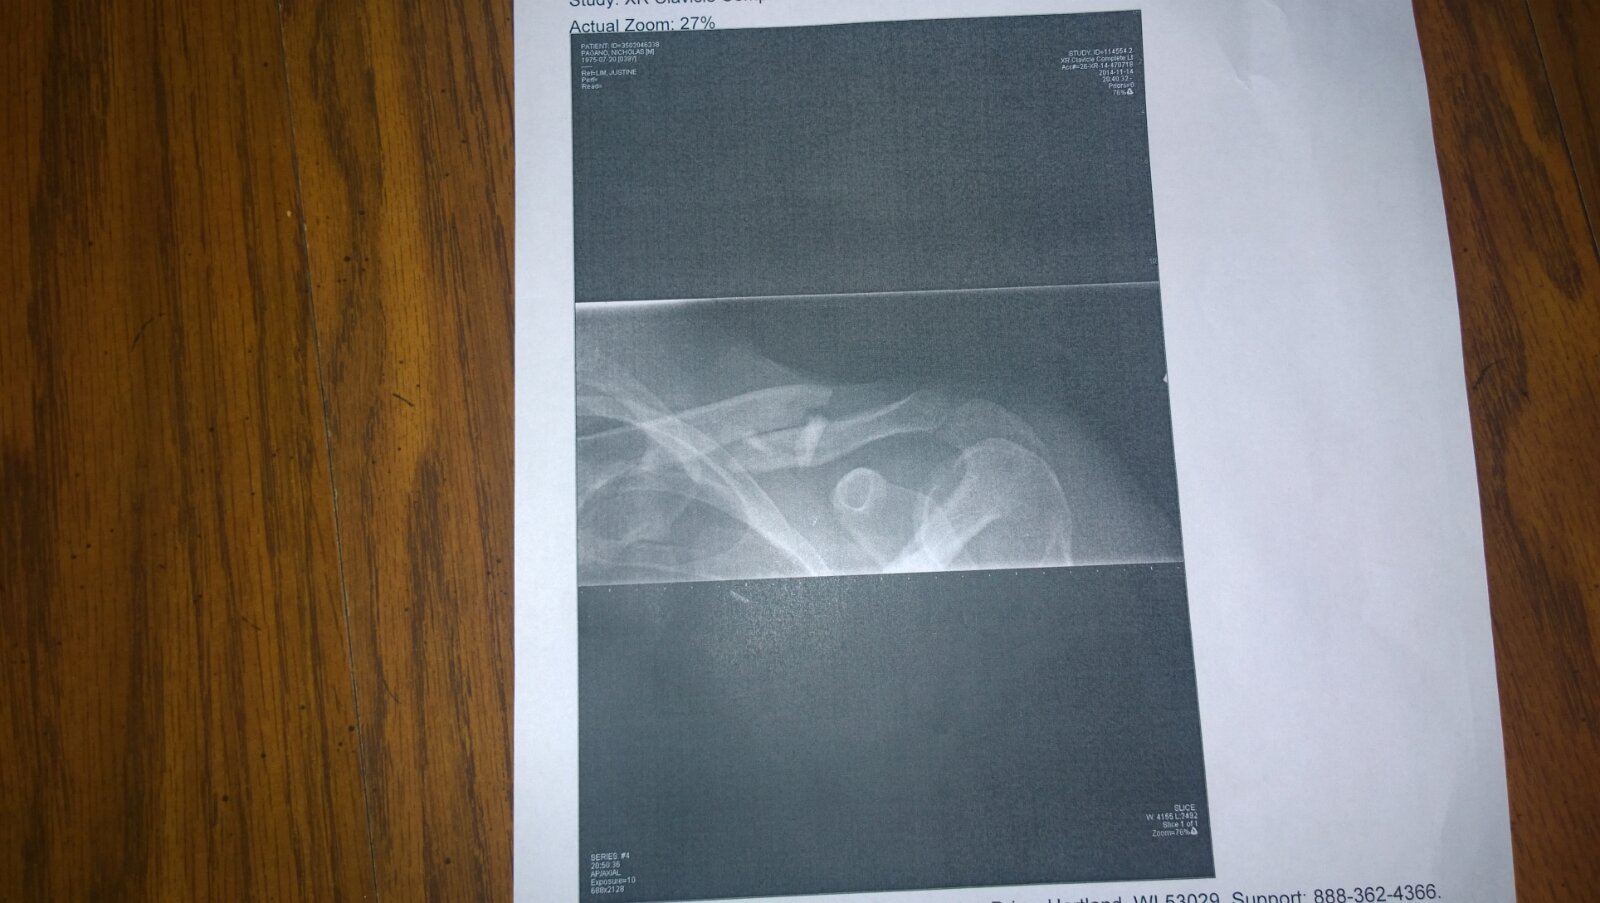

2014-11-15 11/15/14

November 15th